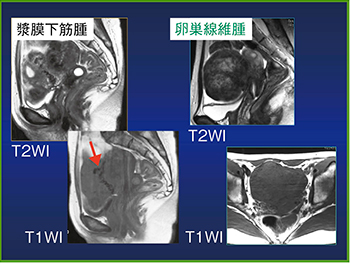

婦人科領域では,子宮近くに腫瘤が認められれば卵巣腫瘤,卵巣囊胞と診断しがちであるが,他臓器由来の腫瘤の可能性もあることに留意したい(図7,8)。

造影MRIで,直腸の粘膜下腫瘍のGIST(消化管間質腫瘍)が直腸前方に圧排されている場合も,卵巣腫瘍と間違える可能性がある。

図7 MRIのBeak Sign

発生由来の臓器がくちばし状に変形する。

図8 MRIのBridging Vascular Sign

子宮に隣接する腫瘤の間に多数の血管がある場合は子宮由来の腫瘍である可能性が高い。(5cm以上43%,7cm以上85%)